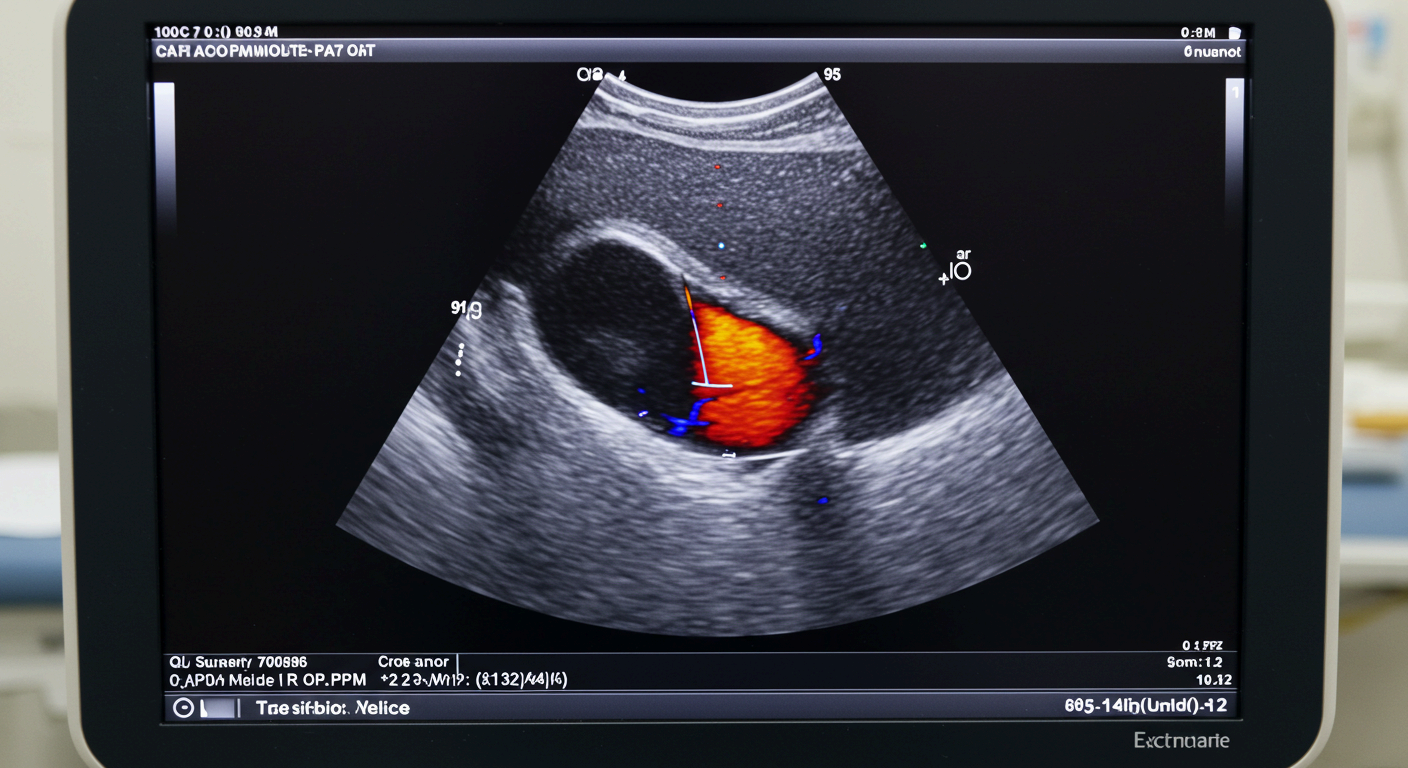

경동맥 초음파(경동맥 도플러 초음파)는 목에 위치한 경동맥의 상태를 확인하는 비침습적 검사로, 뇌로 가는 혈류가 원활한지 확인하고 뇌졸중 위험을 조기에 진단하는 데 중요한 역할을 합니다.

경동맥 초음파는 고주파 음파를 이용해 목 부위 혈관의 구조와 흐름을 영상으로 보여주는 검사입니다.

특히 도플러 초음파 기능을 활용하면, 혈류의 속도와 방향까지 정밀하게 측정할 수 있어 혈관이 얼마나 좁아졌는지(협착률)도 확인할 수 있습니다.